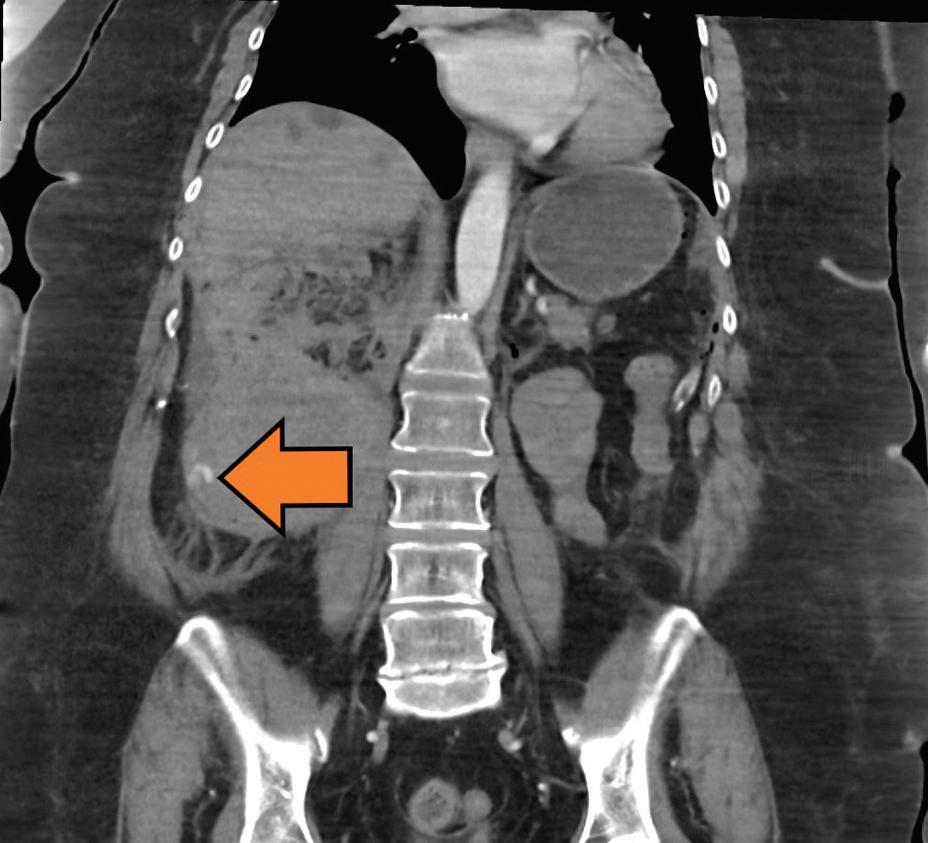

PH je jedn ou z nejčastějších a nejnáročnějších komplikací spojených s vytvořením stomie, vč. ileálního konduitu (obr. 1 a 2). Je definována jako protruze břišních orgánů skrze defekt v břišní stěně v bezprostřední blízkosti stomie [3]. Výskyt PH se u pacientů s ileálním konduitem pohybuje dle literatury v širokém rozmezí 10– 65 %, přičemž až 30 % z nich může vyžadovat chirurgickou intervenci kvůli bolestem, únikům moči, obtížím s lepením stomického sáčku nebo zánětům a podráždění kůže [4,5].

Obr. 1. Pacient s parastomální hernií po otevřené radikální cystektomii s použitím ileálního konduitu.

Fig. 1. Patient with parastomal hernia following open radical cystectomy with ileal conduit.

Obr. 2. Nález na počítačové tomografii u pacienta s parastomální hernií po otevřené radikální cystektomii s použitím ileálního konduitu.

Fig. 2. Computed tomography finding in a patient with parastomal hernia following open radical cystectomy with ileal conduit.